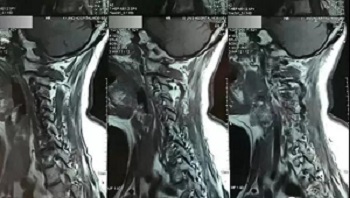

八、拍片子时,如果一张片子上有两张图像的时候,合起来拍一张,分开再各拍一张(如以下三张)

九、翻拍磁共振图像时,因为磁共振片子很大,而且一张片子上有很多图像(如下图),所以,单纯的拍一张片子,因为手机拍摄,像素以及翻拍质量不好,且放大后图像会发虚,细节看不清楚,所以,基本上是没用的,对于医生阅片来说,质量太差,不能获取图片上的有效信息。

十、因此需要将磁共振的一张片子,进行分区域局部放大拍摄,尽可能的将片子上的细节拍摄清楚,将一张磁共振片子进行分区。

十一、将分区的磁共振图像,按顺序进行拍摄,即可获取如下比较有价值的清晰图片